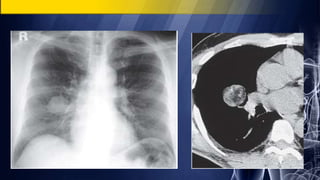

PA chest radiographsdemonstrate a well defined spherical pulmonary mass of lobular contours in the left lung Contrast-enhanced chest CT (mediastinal window) at the level of left atrium demonstrates a heterogeneously enhancing mass with irregular central low attenuation, representing necrosis. The mass abuts central bronchi medial and the adjacent pleura laterally 65-year-old man with cough and chest pain Lung Cancer

• 45.